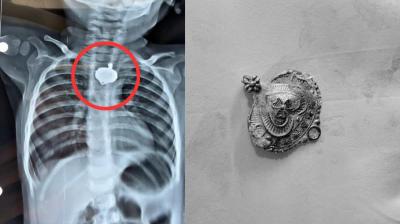

बड़वानी में 9 माह के बच्चे की आहार नली में फंसा मंगलसूत्र, डेढ़ महीने बाद एक्स-रे से खुलासा

24 Nov, 2025 08:30 AM IST | THEKHABARMIRCHI.COM

बड़वानी: रविवार को जिला अस्पताल में एक बेहद संवेदनशील और हैरान करने वाला मामला सामने आया. जब 9 माह के एक बच्चे के गले में मंगलसूत्र फंसा हुआ देखा गया. घटना...